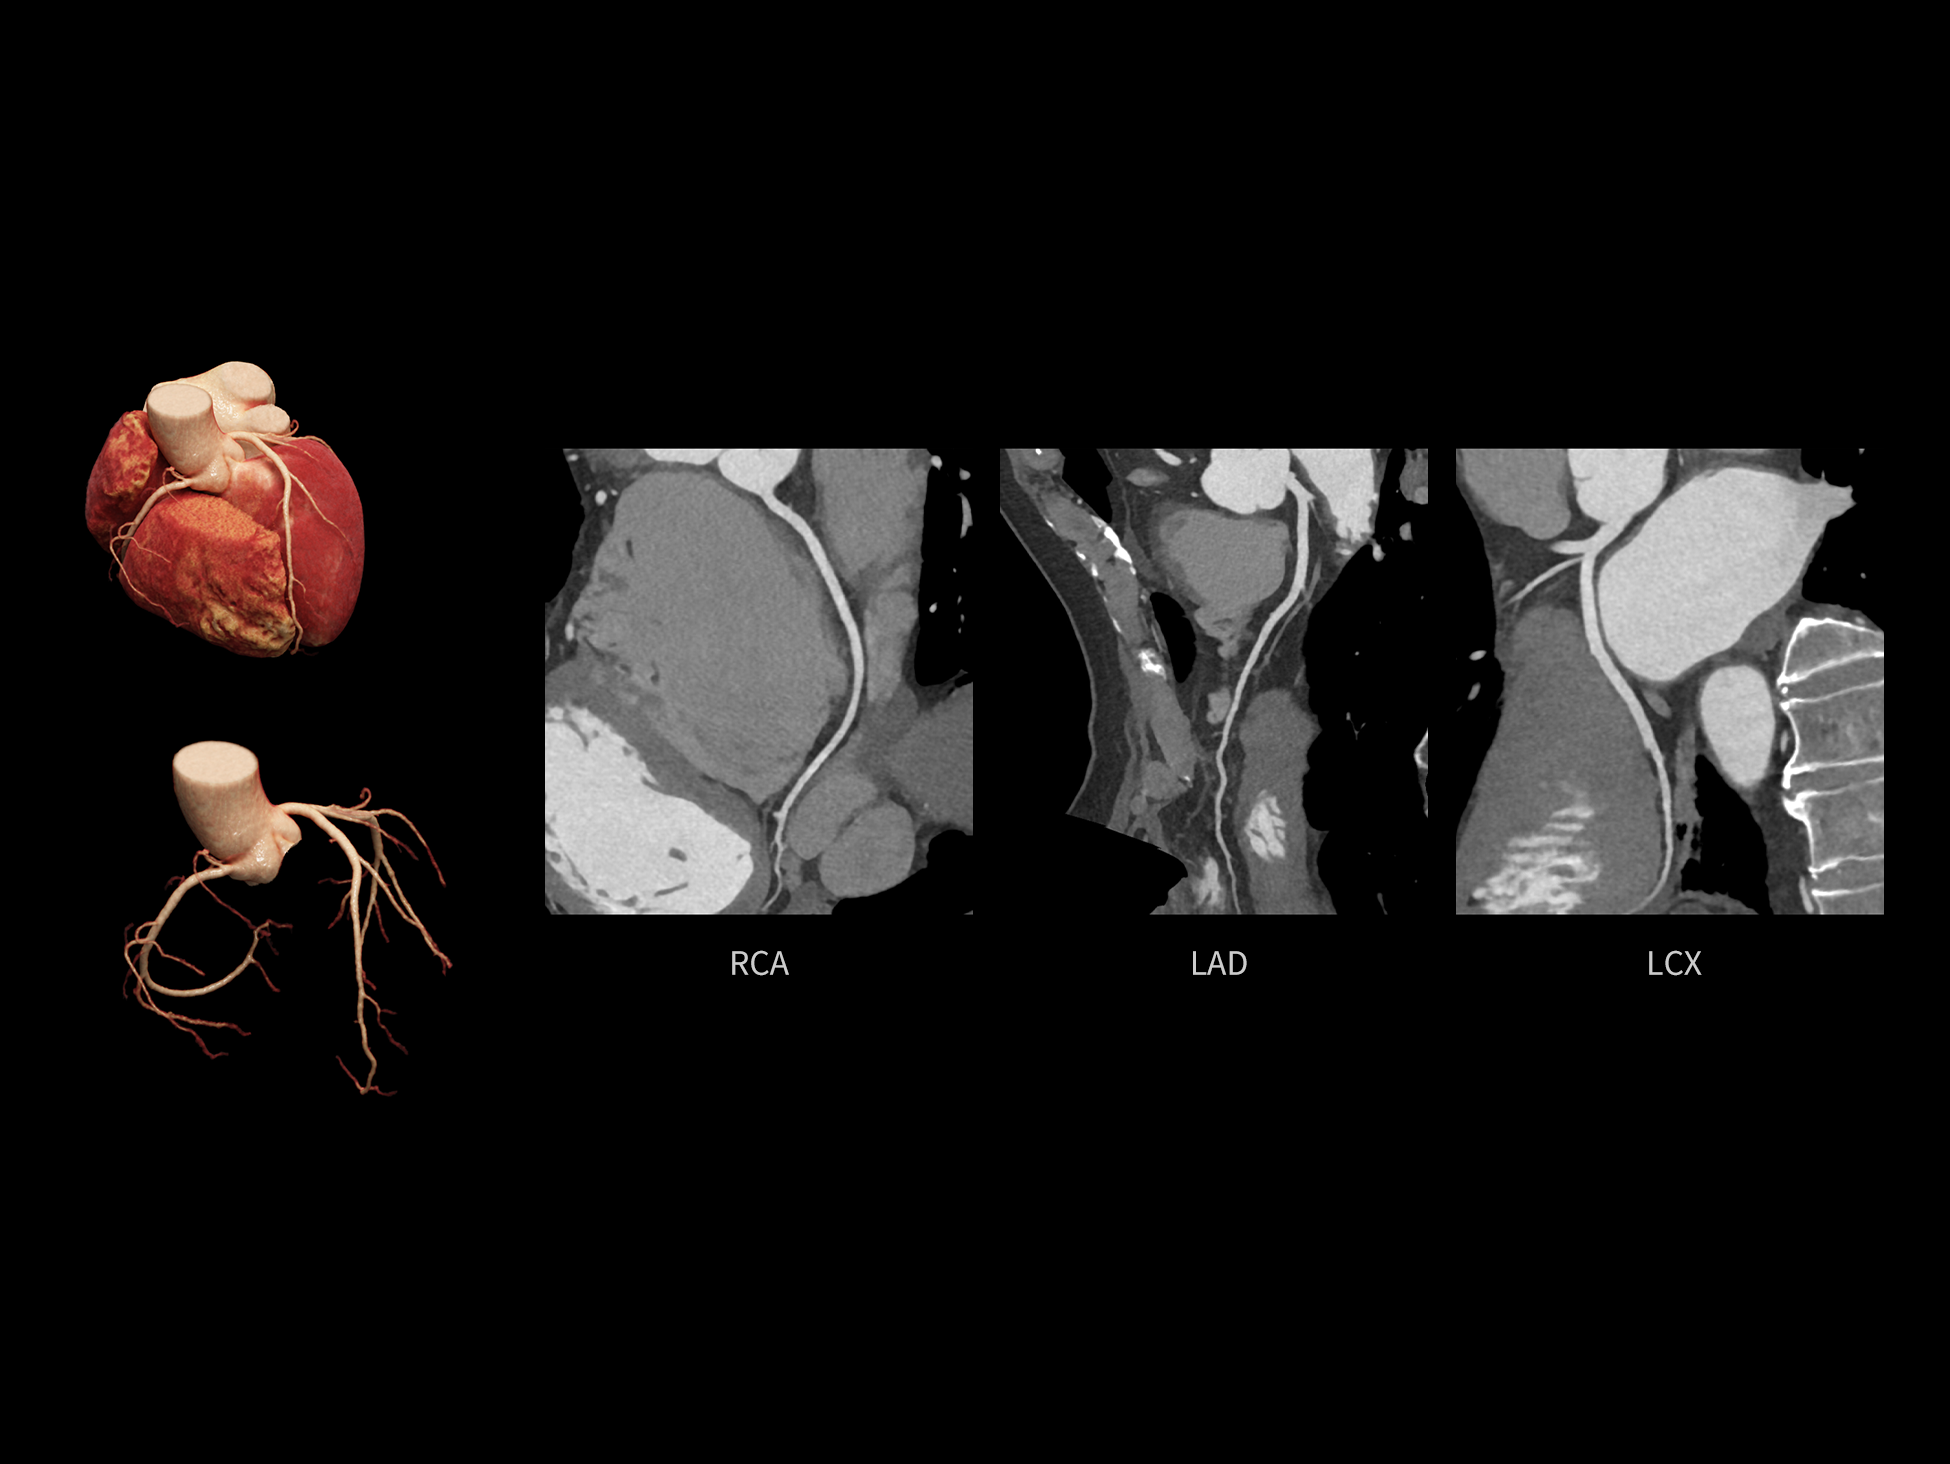

CardioCapture 2.0 通过“识别–追踪–建模–校正”的完整流程,精准分割心脏结构,动态追踪运动轨迹,并构建多时相运动场,最终实现冠脉、瓣膜、心肌及心室结构的同步校正,清晰洞见每一次心跳细微变化,真正将心脏动态掌握于毫秒之间。

CardioCapture 2.0 在目标时相前后重建多时相影像,通过深度学习网络精准提取冠脉中心线,进而建立时相间运动模型,实现对冠脉分段图像的精准运动校正。

冠脉运动校正